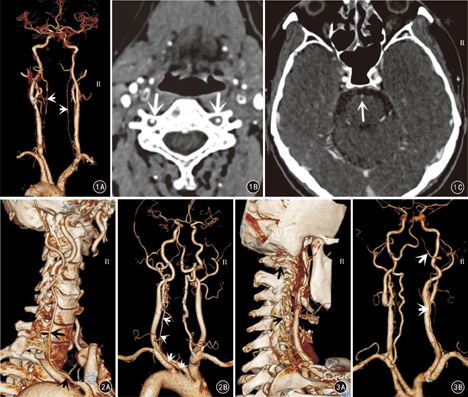

VA的变异包括管径发育细小(图1,图2,图3)、起源部位变异(图2、图4)、各节段行程变异(图2,图3,图4,图5,图6,图7)、数目变异(图4)、分支和异常吻合变异(图5)等。单一变异以一侧VA发育细小或狭窄形成两侧VA不对称最为多见,有66例(33.0%),其中右侧VA细小形成的左侧优势型VA 42例(右VA管径小于3 mm者31例),左侧VA细小形成的右侧优势型VA 24例(左VA管径小于3 mm者19例)。19例MCV中,有12例系由双侧细小的VA(图1)或一侧细小VA合并其他类型变异形成(图2、图3)。

本组有28例(14.0%)30条VA共34个部位表现为不同节段的多种行程变异,如双侧VA分别经不同水平的颈椎横突孔上行入颅(图2、图4、图7);或出C2横突孔后未经过C1横突孔,直接经C1和C2后侧椎弓间进入椎管,形成所谓"C2节段性VA"(图5、图6);或行程中出现折曲向下位椎体内疝入形成椎体动脉环(图6);或出C1横突孔后向C1侧块嵌入,经完整或不完整的骨桥内入颅(图3)等。其中15例(7.5%)行程变异合并其他类型和部位的变异表现为MCV,其中6例(3.0%)同时存在2个部位的行程变异(表2),是最常见的MCV组成类型。

VA起源变异是指VA一侧或双侧起自除同侧锁骨下动脉以外的动脉分支,较常见的是直接起自主动脉,同时多伴有行程的变异(图2、图4)。本组有5例(2.5%,5/200)左侧VA起自主动脉弓,均伴行程变异等表现为MCV。见表2。